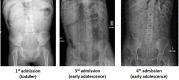

Hirschsprung's disease (HD) is one of the most well-known gastrointestinal motility disorders. Diagnosis and management of other lesser-known motility disorders are often challenging and tedious. We describe a teenager who was severely constipated from birth and needed intensive care admissions for life-threatening enterocolitis. She also had concomitant anal stenosis. Several rectal biopsies were unable to yield a conclusive diagnosis. Surgical level of resection had to be identified based on the motility of the bowel as determined by transit studies using oral ingestion of a milk feed labelled with Technetium-99m colloid. After completion of all operative stages, histopathological examination of the excised specimens concluded that she had short-segment HD associated with reduced interstitial cells of Cajal in the large bowel. She is currently continent, evacuating voluntarily approximately four times a day and is relieved of all her symptoms.